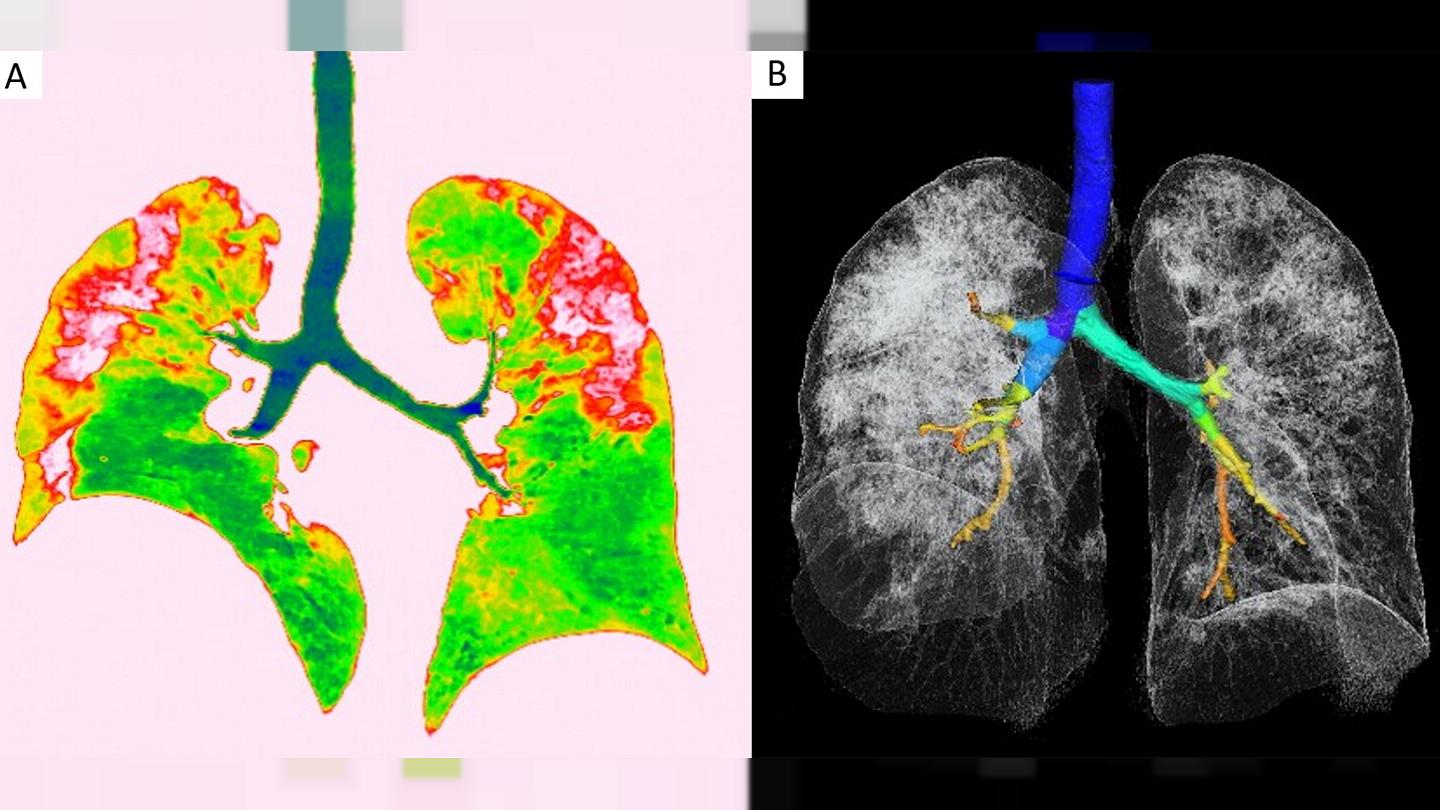

Фото рентгеновских снимков поражения легких при COVID-19

На фотографиях рентгеновских снимков видно, как вирус воздействует на легочную ткань. Характерные признаки поражения легких включают пятна, инфильтраты и наличие жидкости внутри легочных альвеол.

Фото рентгеновских снимков помогают врачам и специалистам визуально определить степень поражения легких и принять соответствующие меры лечения и поддержки пациента.